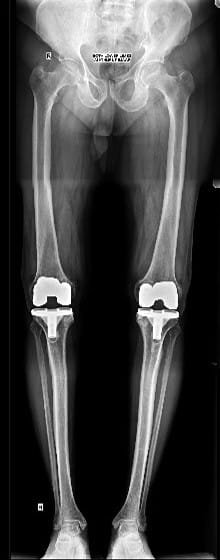

Although there has been an attempt to perform knee replacement in the 19th and early 20th century, Total Knee replacement surgery has come a long way since 1970s with continuous improvement in the design of implants and fixation techniques. Success from Charlney’s hip replacement surgery got surgeons and engineers interested again leading to modern-day implants. It has been successfully being performed worldwide from 1980 onwards. Diseased part of femur and tibia are removed using special instruments and metal implants mimicking design of femur and tibia are inserted using antibiotic-laden polymethyl methacrylate (bone cement). A polyethylene inset is fixed onto the tibial implant thus allowing movement at the knee joint. The undersurface of patella may be replaced with a patellar button in some cases. Due to improved technique and implant design, this surgery has gained immense popularity and has given a new lease of life for the patients suffering with arthritis of the knee joint. Patients can walk comfortably with the help of support following surgery and aren’t dependent on others for day-to-day life activities. Quality of postoperative care in recent times has further boosted the confidence among the patients undergoing this surgery. Patients are taught to strengthen the thigh muscle post-operatively and encouraged to become mobile. Gradually, they learn to climb stairs and later they walk around independently without any aided support. It is recommended that patients should not sit on the floor or squat. This helps maintain the longevity of the implants. As per the American Association of Orthopaedics, success rate of total knee replacement after 15 years is almost 90% and at the end of 25 years is almost 82%.

In total knee replacement surgery, we remove the damaged area over the femur, tibia and patella in the knee joint. It is replaced it with metal implants which are in the shape of these bones. These metal implants are fixed over your bone with the help of bone cement. Implants come in various sizes and you will get the best fit suited for you.